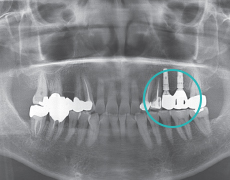

Вторичная процедура (Оссеоинтеграция и соединительный абатмент)Устанавливается имплант и абатмент.

ПротезированиеУстановить коронку на абатмент для завершения процедура.